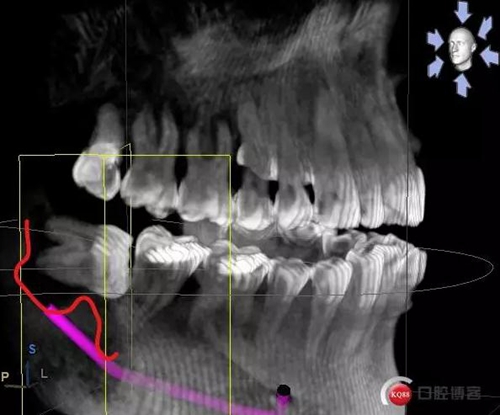

X線及CBCT檢查:47、48根尖周區(qū)大面積低密度影像,波及下牙槽神經(jīng)管,部分區(qū)域至神經(jīng)管以下。CBCT顯示神經(jīng)管走形于47根尖炎癥區(qū)下方(已侵犯)48炎癥區(qū)頰側(cè)(已侵犯)

術(shù)前CBCT分析

術(shù)后影像分析